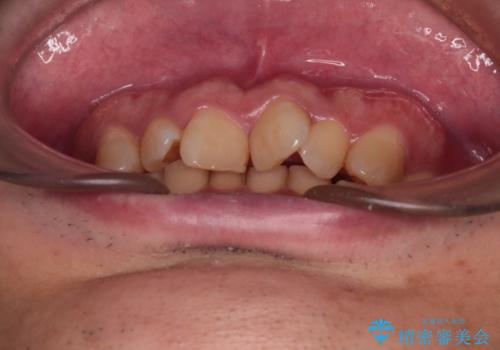

骨格性のディープバイト 補助装置を併用したワイヤー矯正治療で咬み合わせを改善

骨格的に上顎骨がやや前方にあり、それが原因で下顎前歯が隠れるほどのディープバイトになっている状態でした。

補助装置を用いて、上顎大臼歯を積極的に後方移動させながら、ディープバイトを改善していくこととしました。